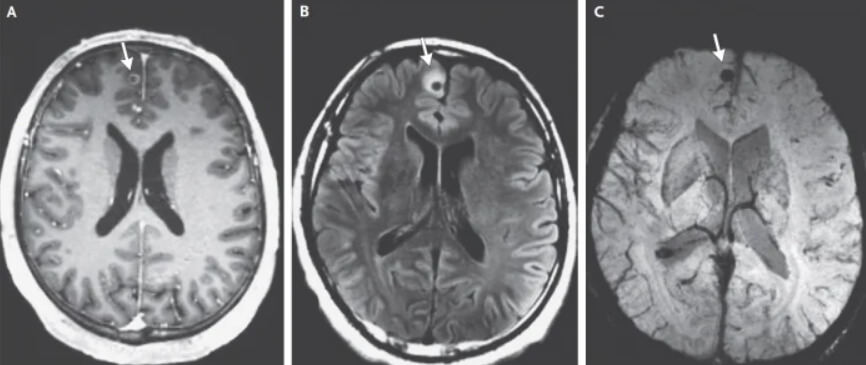

По данным издания Science Alert, найти причину припадков у мужчины удалось только после изучения его биографии. Оказалось, что примерно 20 лет назад он жил в одной из сельских местностей Гватемалы. На снимках его головного мозга врачи обнаружили несколько кист — так называются полости в тканях или органах, которые имеют стенки и содержимое. В ходе дальнейшего изучения оказалось, что эти образования остались в результате жизнедеятельности паразитических свиных цепней (Taenia solium).

Пораженные участки мозга 38-летнего мужчины

Если говорить по-научному, мужчина пострадал от нейроцистицеркоза. Так называется болезнь, которая возникает при заражении человека свиным цепнем. Считается, что это заболевание угрожает здоровью миллионов людей по всему миру. В некоторых источниках говорится, что из-за свиных цепней ежегодно умирает по 50 000 человек, а выжившие остаются инвалидами на всю жизнь. Оказавшиеся в головном мозге личинки вызвали у мужчины эпилепсию, потому что давили на его некоторые области.